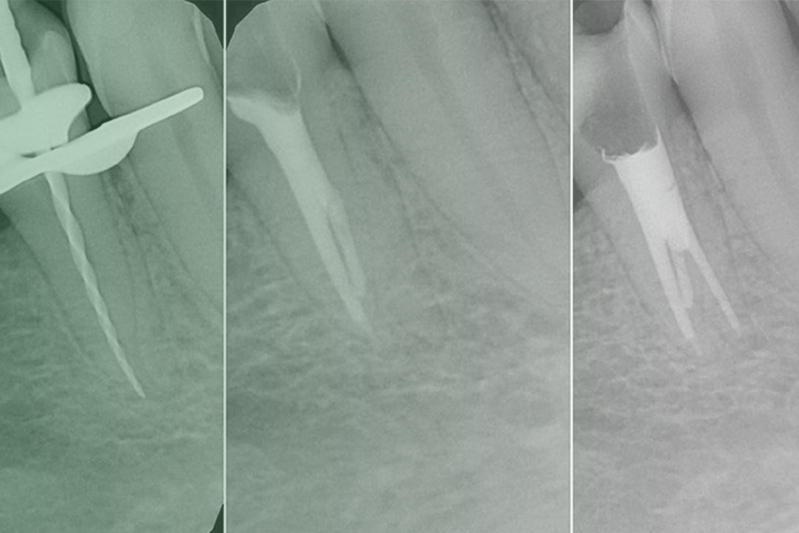

Клинический случай. Эндодонтия

03 марта 2020